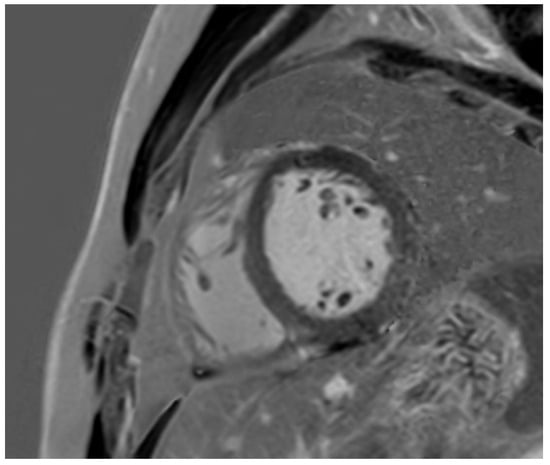

Tissue characterisation with cardiac MRI also plays a key role in athletes with a suspicion of HCM. Post-contrast imaging with late-gadolinium enhancement (LGE) is used to detect macroscopic replacement fibrosis (Figure 3). The presence of fibrosis is diagnostic of a disease process, often patchy and present in hypertrophied segments. Extensive LGE has also been associated with an increased risk of ventricular arrhythmias and SCD [67,68,69]. LGE is, however, only present in 60% of HCM cases [68,70], implying that the absence of fibrosis should not preclude labelling an athlete with HCM. T1 mapping has an important role in LGE-negative HCM cases. Myocyte hypertrophy, rather than expansion of the extracellular matrix, often leads to lower T1 values, especially in endurance and male athletes. This provides a valuable insight into the pathophysiological process of athletes with LV hypertrophy [71,72,73]. Pathological LVH, on the other hand, is positively correlated with ECV, suggesting that an increase in the extracellular matrix is the main contributing factor towards an elevated LV mass [74]. T1 mapping certainly holds promise, yet it requires extensive validation in large athletic cohorts with HCM. LGE and mapping sequences may also play a diagnostic role in HCM phenocopies when cardiomyopathy coincides with extracardiac manifestations. There is a typical abnormal post-contrast myocardial nulling in cardiac amyloidosis. T1 values are, conversely, significantly reduced in Fabry’s disease [75].

Figure 3. Caucasian male soccer player presenting with inferolateral T-wave inversion on ECG. SSFP cine imaging (A) showing apical hypertrophy, with evidence of apical fibrosis on post-contrast imaging (B,C).